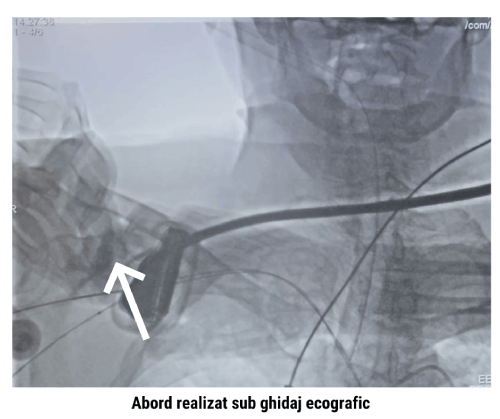

În ziua intervenției, sub anestezie generală și ghidaj ecocardiografic transtoracic, echipa a abordat artera subclaviculară dreaptă prin puncție percutană, realizată sub control ecografic. Au fost montate dispozitivele de preînchidere ProGlide, apoi teaca necesară procedurii.